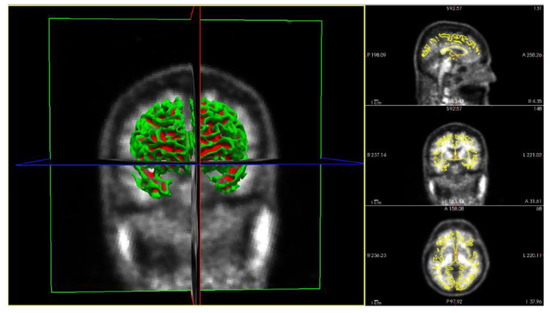

3.1. Obtention of Imaging Derived Features after PVC

This part of the method deals with the obtention of the different SUVR values, obtained for all ROIs in the images by applying several PVC methods. The imaging pipeline has a double path, one for processing the PET studies and another for the MRI studies. The MRI path is devoted to obtaining the ROI to compute the SUVR values on the PET after PVC correction. For this purpose, the Desikan–Killiany atlas [35] was employed, Figure 3 shows the different stages of the MRI process [32]. The atlas color labels [35] are shown in Figure 3c,d.

Figure 3. Coronal image of a patient from the study. (a) T1-weighted Magnetic Resonance Imaging (MRI—T1W). (b) MRI output after processing stages: Motion Correction and Conform, Intensity Normalization, Remove Neck and Skull Strip. (c) MRI output after applying Talairach transform computation and Cortical Parcellation Desikan-Killiany, an atlas that will permit us to obtain the values of Standard Uptake Value Ratio (SUVR) on the same patient from the PET image. (d) Three-dimensional reconstruction of the atlas from (c) using the color map of Desikan-Killiany atlas.